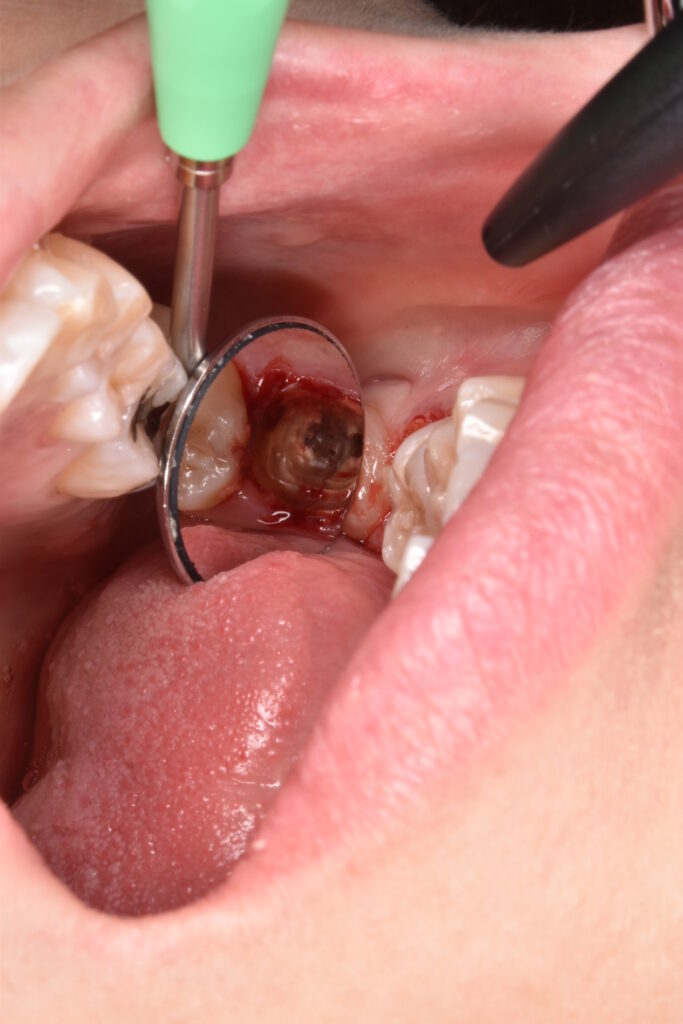

左右両隣は歯に1ミリの鋼線を使用して矯正用のゴムで折れてしまった歯を牽引しているところです。

仮の歯を貼り付けて初回の治療は終了です。

裏側はこんな感じです。舌感は悪いですが、しばしの辛抱です。汚れが溜まりやすいので衛生面には注意が必要なのと、仮歯は張り付いているだけなので、とても取れやすいです。